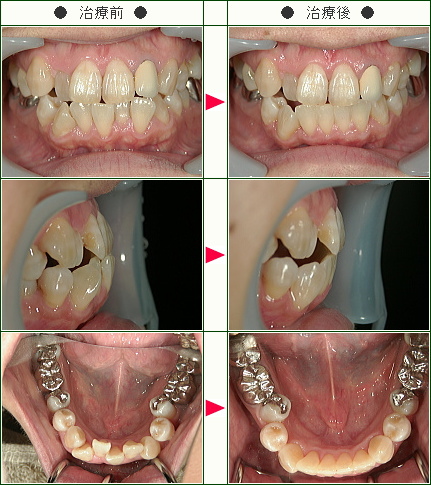

☆デコボコ症例(T・M様 40歳 男性)

▼患者様の感想

以前(小学生の時)抜歯の矯正を受け、診察のたびに締め付けられるので痛みがひどく歯が浮いたような感じになり、チンキャップを一時期用いていたためとても大変でした。

その経験があるので、今回は部分矯正ということもあり、痛みもマウスピースの不快さ(特に食事のとき)もさして負担ではありませんでした。

下の歯で一本内側に倒れて舌が当たってしゃべりづらい感じがあり、部分矯正をお願いしました。

保定に入る段階で治療開始前の歯型の模型を見て、思い切って治療をして本当に良かったと実感しました。

料金が一括で治療終了まで基本的に追加がないというのも、治療を受けることを決める際にとても安心できました。

親切、丁寧、わかりやすく、システマティックです。